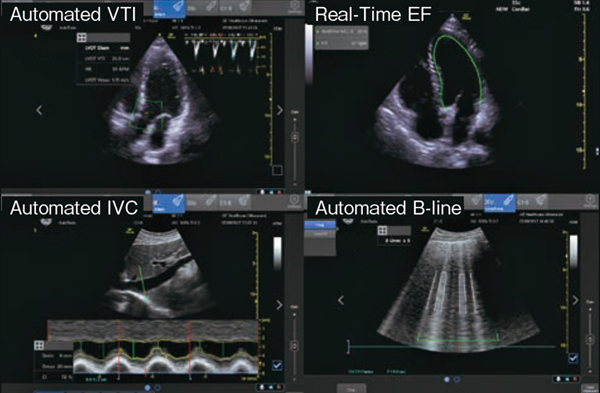

先に紹介したVenueおよびVenue Goは,主に救急科のニーズに合わせてAI技術を用いて開発した「Automated VTI」「Automated IVC」「Automated B-line」「Real-Time EF」の4つのAuto Toolを有している。それぞれ,プローブを患者に当て,指定のBモード画像を描出してAuto Toolのボタンを1つ押すだけで,リアルタイムに計測値を得られるアプリケーションである。

■VenueおよびVenue Go搭載の4つのAuto Toolの紹介

Real-Time EFは,心尖部四腔断面のスキャン中に,リアルタイムで左室駆出率(EF)を自動計測する機能である。Automated VTIは,心尖部より左室流出路を描出し,ワンタッチで自動的に速度時間積分(VTI)を算出する。左室流出路径を入力すれば,心拍出量(CO)も簡便に算出可能である。また,VTIの経時的変化をグラフ表示することも可能である。Automated IVCは,ワンタッチで簡便に下大静脈(IVC)の呼吸性変動を計測する。自発呼吸,人工呼吸の切り替えも可能である。Automated B-lineは,リアルタイムでB-lineをハイライトし,カウントする。フリーズ後,スキャンした間に最もB-lineが出現したフレームを表示する機能である(図2)。

図2 4つのAuto Tool